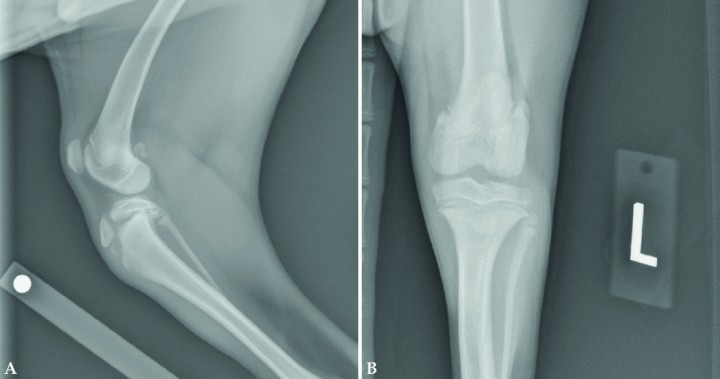

<p>Fractura a nivel de la línea de crecimiento de la tibia proximal en un cachorro de 4,5 meses de edad. En la proyección mediolateral (Fig. 4A) se puede observar que el fragmento proximal de la fractura lo componen la meseta tibial y la tuberosidad tibial. No existe línea de fractura entre la meseta tibial y la tuberosidad tibial. Nótese el desplazamiento caudal de la meseta tibial en relación al resto de la tibia. En la proyección craneocaudal (Fig. 4B) se observa un incremento de la opacidad de los tejidos blandos a nivel de la línea de crecimiento, aunque no existe desplazamiento de la fractura medio-lateralmente.</p>

Fractura a nivel de la línea de crecimiento de la tibia proximal en un cachorro de 4,5 meses de edad. En la proyección mediolateral (Fig. 4A) se puede observar que el fragmento proximal de la fractura lo componen la meseta tibial y la tuberosidad tibial. No existe línea de fractura entre la meseta tibial y la tuberosidad tibial. Nótese el desplazamiento caudal de la meseta tibial en relación al resto de la tibia. En la proyección craneocaudal (Fig. 4B) se observa un incremento de la opacidad de los tejidos blandos a nivel de la línea de crecimiento, aunque no existe desplazamiento de la fractura medio-lateralmente.